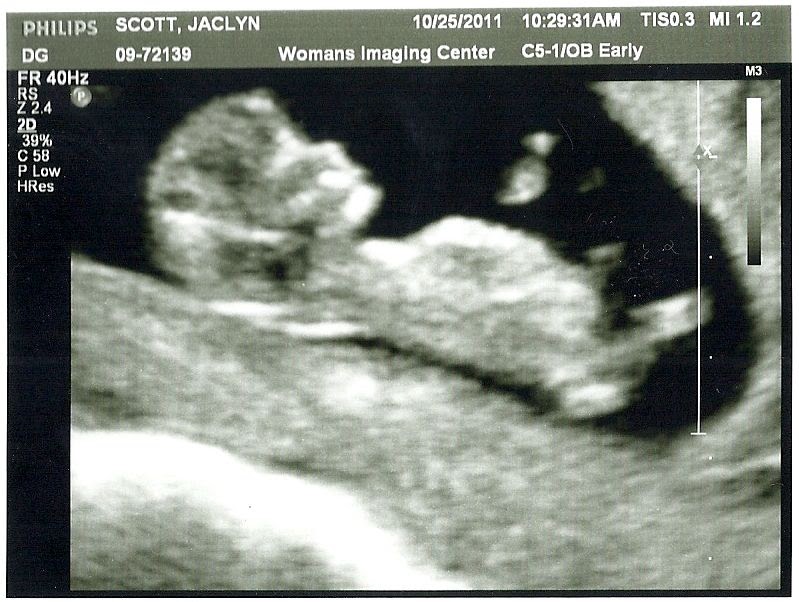

On this 3d ultrasound scan, you can already clearly see a little face has formed.

On this 3d ultrasound scan, you can already clearly see a little face has formed. By the end of this week, your baby�s external genitals will start developing. The basic anatomy of the fetus is apparent at this point, and the examining physician… Normal 11 week baby ultrasound. This page shows typical 3d ultrasound images from 11 to 36 weeks.

Your 11 week ultrasound is looking more and more like a baby, and watching baby flop around like a little fish out of water always creates a chuckle for us spectators. Your baby is no longer called an embryo. As usual, we start with the maternal organs first then the baby… remember the 11 weeks scan is still done transvaginally. Along with developing sleeping and waking cycles, he or she is growing more into what your newborn will look like at birth. At this stage, the baby has put on some weight and filled out to make features more visible, yet still enough fluid in front of baby’s face to obtain great images. 38 weeks.